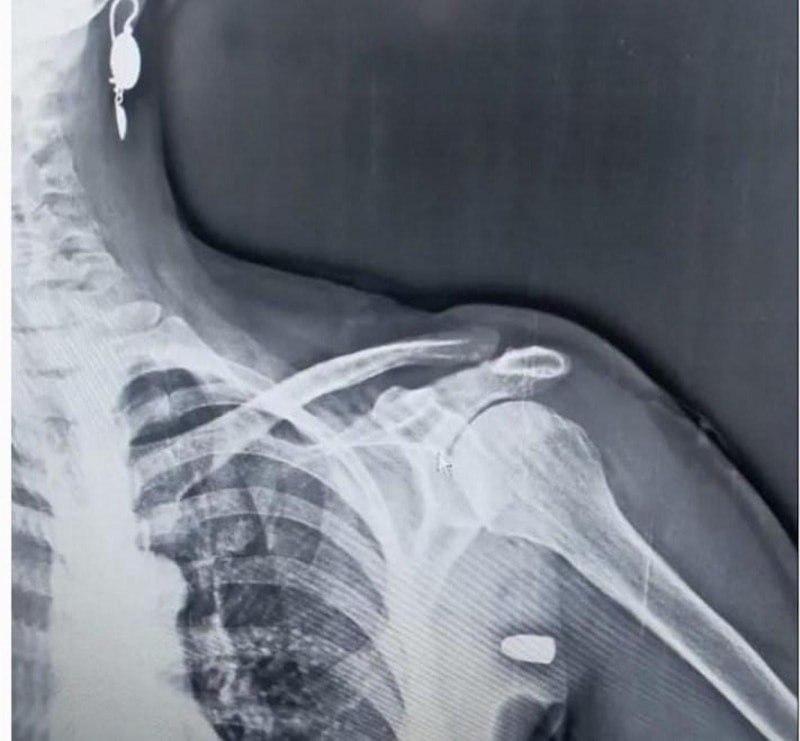

Trabzon’un Tonya ilçesinin Karaağaç Mahallesi yakınlarındaki Hırsafa Yaylası’nda 2022 yılının Kasım ayında ot biçen Asiye İnce (59), sol omuz bölgesinden giren yorgun mermi ile yaralandı. Hastanede tedavi altına alınan İnce mermi çekirdeği ameliyatla çıkartılması sonucu sağlığına kavuştu.